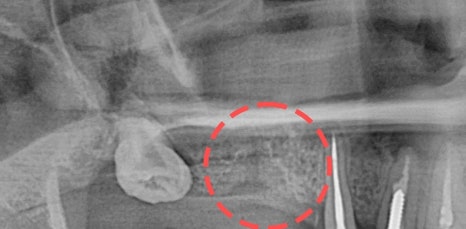

특히 위쪽 어금니 쪽이 상실 되어 임플란트 시술을 진행해야 하는데 잇몸 뼈가 부족한 상태라면 추가적으로 상악동거상술을 함께 진행해야 했어요. 상악동이란 코 양옆에 위치하고 있으며 뼈 속에 비어 있는 공기 주머니로 두개골의 무게를 줄여주는 곳이었어요. 상악동은 아주 얇은 막으로 둘러 쌓여 있으며 상악 쪽의 잇몸 뼈가 부족한 상태로 임플란트를 식립 하게 된다면 상악동 막이 찢어지거나 천공이 생길 수 있었어요.

상악동에 천공이 생기게 된다면 염증으로 인해 부작용이 생길 수 있었어요. 그렇기 때문에 환자 개개인마다 크기와 위치가 모두 다른 상악동의 위치와 잇몸 뼈의 두께를 정확히 파악하는 것이 중요했어요. 정밀 검사 후 임플란트를 식립 하기에 잇몸 뼈의 양이 부족하다는 진단이 나오게 된다면 얇은 상악동 막을 들어올려 준 후 필요한만큼의 뼈 이식을 진행해 주는 방법이 상악동거상술이었어요.